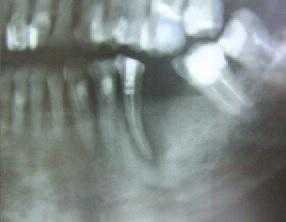

Оценку эффективности лечения ЭПП мы проводили на основании клинических и рентгенологических критериев (рис. 3): наличие жалоб на боли при накусывании, подвижность, гноетечение из кармана или фистулы; на основании рентгенограмм оценивали состояние костной ткани пародонта и периапикальной области.

Рис. 3. а - ЭПП в области зуба 47; б - восстановление костной ткани в периапикальной области зуба 47 и стабилизация уровня костной ткани альвеолярного отростка после проведенного лечения.